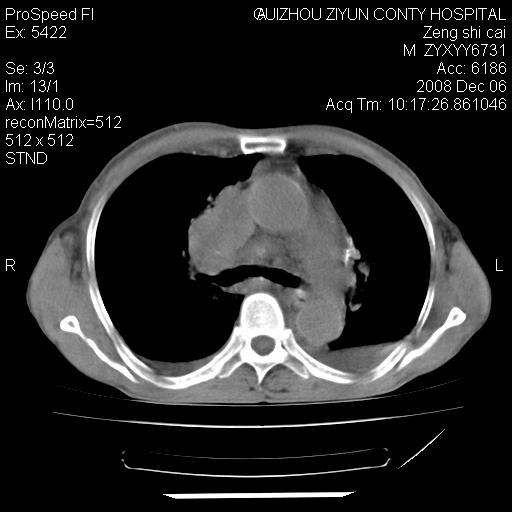

标题: CT16961:M、71岁,咳嗽半年,无血痰;胸片示右肺占位。 [打印本页]

标题: CT16961:M、71岁,咳嗽半年,无血痰;胸片示右肺占位。

1)考虑右肺上叶纵隔型肺癌伴纵隔淋巴结转移。2)心包积液,双侧胸腔积液。

右肺上叶纵隔型肺癌伴纵隔淋巴结转移。心包积液,双侧胸腔积液。